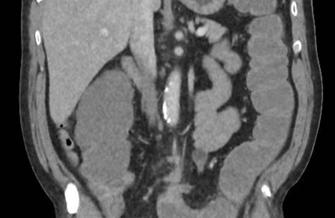

Tumoră stenozantă de colon sigmoid cu evoluție particulară. Prezentare de caz

Asist. Univ. Dr. Ionuţ Simion Coman, Asist Univ. Dr. Violeta Elena Coman, Dr. Cosmin Burleanu, Asist. Univ. Dr. Anwar Erchid, Dr. Ileana Ioana Mușatescu, Șef Lucr. Dr. Gabriel Petre Gorecki, Prof. Univ. Dr. Valentin Titus Grigorean